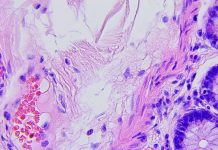

The particular tumour micro-environment and tumour-host interaction come on top of these challenges. The connection of the immune system within the brain exists, but has special characteristics. The tumour microenvironment is strongly immune-suppressive, and most GBMs are evaluated as “cold”, without immune cell infiltration. Furthermore, there is a predominance of myeloid cells, partially infiltrated, partially being microglia from the brain itself.

Neurosurgery and radiochemotherapy are primarily aimed to reduce the tumour volume. Maintenance chemotherapy is aimed to keep control over residual tumour cells. We combined immunogenic cell death therapy (oncolytic virus therapy and modulated electrohyperthermia) during maintenance chemotherapy, and continued with active specific immunotherapy using dendritic cell vaccines and maintenance immunogenic cell death therapy, in combination with modulatory immunotherapy, to improve the overall survival of GBM patients.

To conclude, the role of the Individualised Multimodal Immunotherapy integrated within and after the standard of care to improve long-term overall survival with good quality of life of GBM patients becomes obvious. Immunogenic cell death therapy changes the tumour-host interaction by releasing danger signals within the tumour microenvironment and thereby starting an immunisation process. The dendritic cell vaccines are loaded with antigenic extracellular microvesicles and apoptotic bodies induced by immunogenic cell death therapy, and yielded out of the serum. In this way, the vaccine is loaded with actualised tumour antigens out of residual tumour cells that escaped the radio-chemotherapy and the maintenance chemotherapy. The maintenance immunogenic cell death therapy remains killing potentially appearing new tumour sub-clones thereby including potential novel tumour antigens under the dendritic cell vaccine-induced global anti-GBM immune protection. This treatment strategy is adapted for each patient and each phase of the disease, taking into account dynamic changes in the tumour, in the immune system, and in the tumour-host interaction.